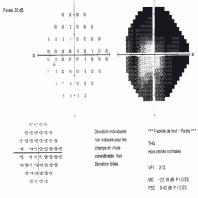

- eFig. 9-18 - Relevé de test de seuil N-30-F

- eFig. 10-15 - Suivi en périmétrie automatisée standard et en Matrix™ d'un sujet de 63 ans présentant un déficit débutant